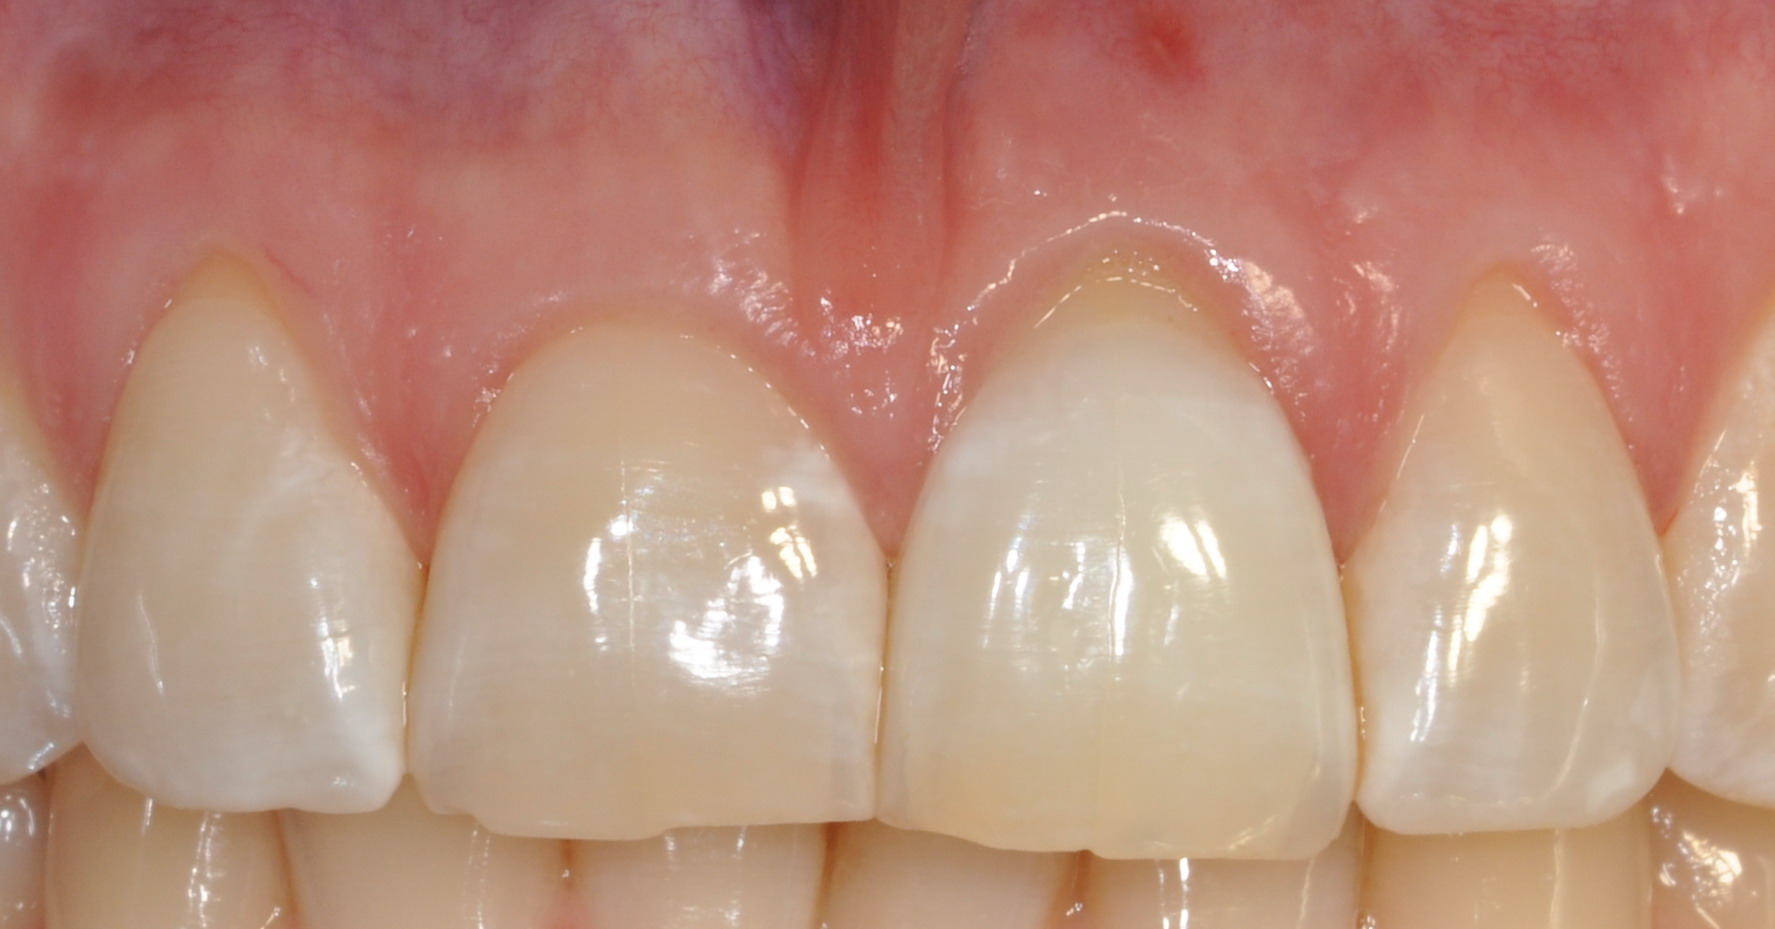

Prima

Dente 2.1 discromico

Dopo

Dente 2.1 dopo aver effettuato lo sbiancamento interno